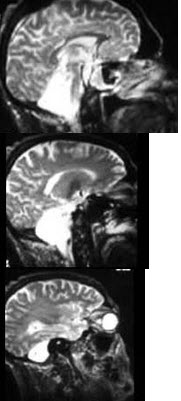

33、单项选择题

患者,女,16岁,四肢活动不灵半年,走路不稳2个月。行MRI检查如下图,最可能的诊断为()

A.室管膜瘤

B.血管畸形

C.Chari’s畸形(Ⅰ型)并脊髓空洞形成

D.枕大孔疝

E.未见异常

34、多项选择题 神经系统发育异常性疾病的常见病因包括()

A.感染

B.药物